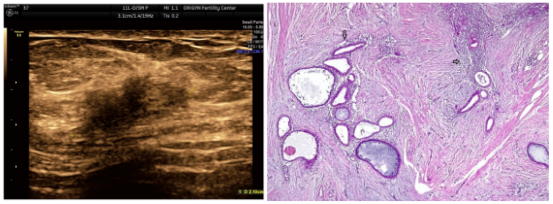

超声显示皮下脂肪内有不规则、不均匀、低回声、边界不清的长方形实性肿块,腹肌有部分浸润,但不能向更深的解剖平面移动(图1)。

图1. 超声图像表现为多发性低回声固体肿块,边界不清

图2. 肿块的组织学显示出子宫内膜腺体和间质(箭头)

患者的切除标本在显微镜下表现为:结缔脂肪组织碎片,有腺体成分和子宫内膜样间质,有胞内和胞外含铁血黄素沉积,淋巴浆细胞浸润和纤维化。因此,推测的腹壁子宫内膜异位症的诊断得到了组织学证实(图2)。